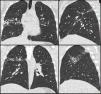

Caso clínicoVarón de 33 años, natural de Guayaquil (Ecuador), rasgos étnicos andinos que reside en España desde el año 2003, año en el que a raíz de presentar un cuadro constitucional, hemoptisis e infiltrados con cavitación en lóbulos superiores se confirma en otro centro enfermedad tuberculosa mediante esputo positivo para Micobacteryum tuberculosis (M. tuberculosis), por lo que se ingresa en centro específico para tratamiento durante 6 meses con isoniazida, rifampicina, pirazinamida y etambutol durante dos meses y luego isoniazida, rifampicina 4 meses más. Tras ello el paciente queda en revisiones periódicas en otro centro donde consta que está asintomático a excepción de esputo herrumbroso desde 2003. En dicho seguimiento se realizó TAC en 2007 que muestra en segmento posterior de lóbulo superior derecho una cavidad periférica de 2cm de pared media e imágenes sugestivas de bronquiectasias cilíndricas. La analítica de esa fecha muestra discreta eosinofilia del 9%. Posteriormente, en 2008 cuando acude a nuestras consultas y ante la persistencia de la expectoración herrumbrosa persistente (que el paciente describe como «sangre» en cuantía de unos 5-10ml/día) se realiza una radiografía de tórax (con hallazgos superponibles a los descritos en el TAC de 2007) (fig. 1) y esputos seriados negativos para bacilos ácido-alcohol resistente y Löwenstein negativo, aislándose en uno de ellos una Brevundimonas vesicularis (B. vesicularis), por lo que se puso tratamiento erradicador con ciprofloxacino 750mg cada 12 horas durante 21 días sin cese de la expectoración herrumbrosa. Ante la persistencia de la clínica se realiza nuevo TAC torácico cuyos hallazgos son idénticos a los del TAC de 2007 (fig. 1) y ante la persistencia de hemoptisis leve pertinaz por supuestas bronquiectasias y tractos cicatriciales localizados se decide lobectomía superior derecha previo estudio funcional respiratorio normal.